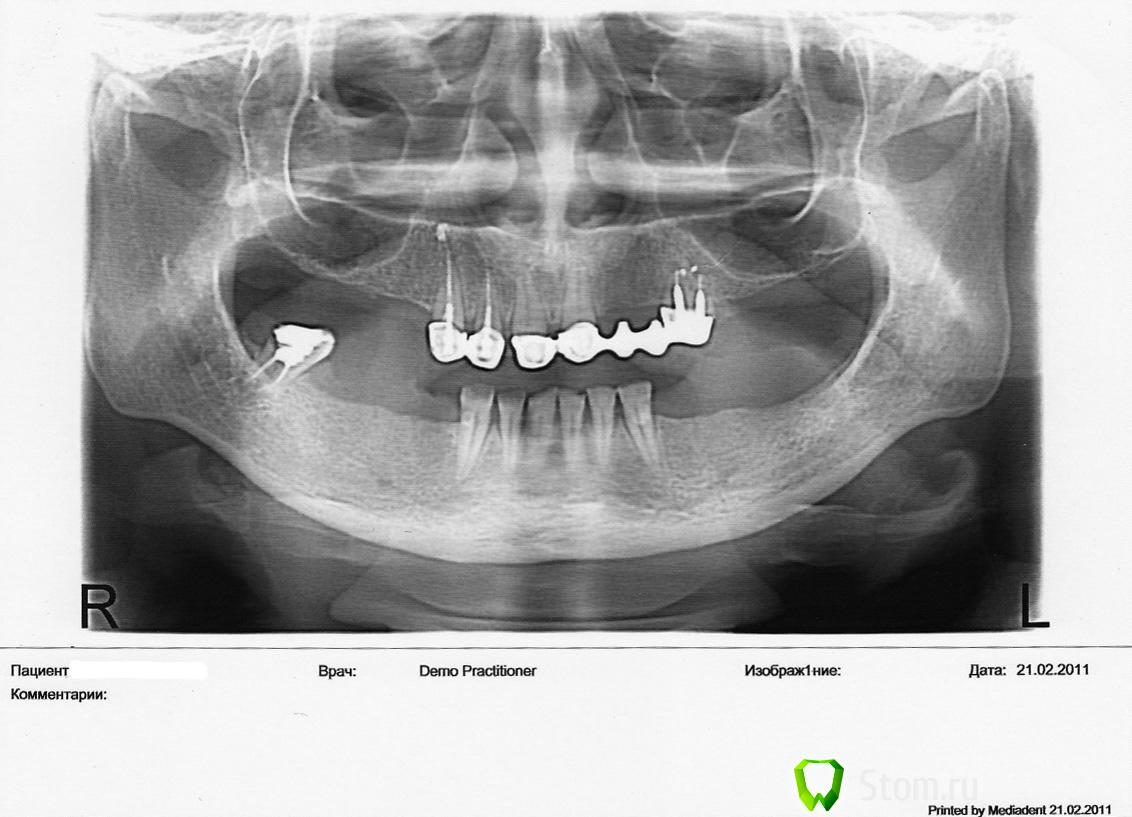

OlenkaN Опубликовано 17 апреля, 2012 Поделиться Опубликовано 17 апреля, 2012 Здравствуйте! Мне 35 лет в положении на 18 неделе. Надо протезироваться, но незнаю как... Были мягкие протезы, но недавно пришлось удалить 2 верхних зуба на штифтах. В одной клинике посоветовали бюгельный протез с аттачменами, в другой сказали что нельзя - большая нагрузка на передние зубы и я могу потерять и их. В моем положении я хочу быстрее решить этот вопрос. Подскажите!!!! Если возникнут вопрос - куда делись все зубы? - я думаю, что это причина первой беременности и собственной глупости. Заранее спасибо. Ссылка на комментарий